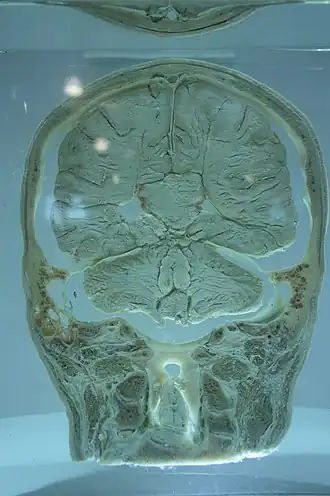

Following the work of John Hughlings Jackson (1835–1911) and David Ferrier (1843–1924) on neurological mapping of functions in the brain, Macewen demonstrated in 1876 that it was possible to use a precise clinical examination to determine the possible site of a tumour or lesion in the brain, by observing its effects on the side and extension of alterations in motor and sensory functions. Thus, in 1876 he diagnosed an abscess in the frontal lobe of a boy, but the family refused permission to operate. When the patient died his diagnosis and localisation were found to be correct.

In 1879 he performed the first successful intracranial surgery where the site of the lesion (a left frontal meningioma) was localized solely by the preoperative focal epileptic signs (twitching of the face and arms in the opposite side of the lesion). On the basis of these signs Macewen thought that there was good evidence of an "irritation to the lower and middle portions of the ascending convolutions…in the left frontal lobe". A trephined hole in the skull near the purported site of the lesion showed a big subdural tumour. The patient, a teenage girl, lived for eight more years, and a subsequent autopsy showed no trace of the tumour. He later used this many times to successfully operate on brain abscesses (in 1876) and hematomas and on the spine. This was a great triumph of medicine.

According to one of his biographers, "his thorough knowledge of the natural history of pyogenic diseases of the temporal bone and nasal sinuses, in addition to his clear description of cranial anatomy, as illustrated in his Atlas of Head Sections, were especially important in developing his successful treatment of brain abscess. The X-ray had not yet been discovered; Macewen's diagnosis was based on clinical findings superbly illustrated by his three clinical stages of brain abscess development." (Canale, 1996).

One of his earliest contributions while at the Royal Infirmary, in 1877, was in orthopaedics, by means of the development of the first bone grafts, but also in knee surgery using a special instrument (Macewen's osteotome) both techniques becoming key treatments for the highly prevalent disease of rickets (caused by a lack of Vitamin D). Macewen was interested in the biology of bone and carried out a classical series of experiments on animals in order to determine how bones grow and may be repaired. He developed surgical treatments for mastoid disease and pyogenic cysts of the temporal bone and has identified an anatomical structure in this bone, the foveola suprameatica, which was named MacEwen's triangle in his honour.

His method of surgical removal of lungs became a major medical weapon in the treatment of tuberculosis and lung cancer, thus saving many patients. His name was also immortalised in Medicine in two other instances: the Macewen's operation for inguinal hernia and the Macewen's sign for hydrocephalus and brain abscess.